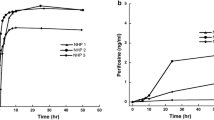

Serum and CSF concentrations were obtained following 22 (median) (min–max: n = 7–41) prior doses of bevacizumab. Bevacizumab administration (10 mg/kg) and measurements in serum were performed 14 days (range 12–15 days) after the previous infusion of bevacizumab. Trough (minimum concentration [Cmin]) and peak (maximum concentration [Cmax]) serum samples (before and after intravenous infusion of bevacizumab) were available for all patients (nsample = 24). Cmin ranged from 77.0 to 305 mg/L (median 144 mg/L), and Cmax encompassed values between 267 and 612 mg/L (median 417 mg/L; Fig. 2).

Left panel: Serum concentrations, measured before and after bevacizumab (BVZ) infusion (vertical red line). Right panel: concentrations in cerebrospinal fluid (CSF), measured on different days following BVZ administration (partly in different dosing intervals). BLQ below the lower limit of quantification

CSF samples were taken when intraventricular therapy was scheduled. In each patient, three (median) (min–max: 3–4) CSF concentrations were obtained during different treatment cycles of bevacizumab within 1–15 days after dosing (see Fig. S1 in the Online Resource [electronic supplementary material] for individual CSF and serum sampling). In CSF, concentrations of 0.01–2.26 mg/L (median 0.35 mg/L) were quantified (ntotal = 38; 3–4 samples/patient; Fig. 2).

Individual pharmacokinetic parameters were determined for each patient using a previously developed two-compartment model for bevacizumab [23]. The model predicted Cmin and Cmax concentrations reasonably well (Fig. 3; individual profiles: Fig. S2, Online Resource) and was used to describe the serum concentration–time profiles of the patients also at later time points (Fig. 4).

To date, no direct assessment of the extent to which intravenous bevacizumab can reach the CSF has been performed. To address this important clinical question, we measured bevacizumab in serum and CSF and assessed the extent of distribution using population pharmacokinetic modelling and simulation. Serum concentration measurements were available only shortly before and after bevacizumab administration (Cmin 77.0–305 mg/L; Cmax 267–612 mg/L). The observed serum concentrations were in the range of previous studies in children with osteosarcoma [32] and patients with advanced non‑squamous non‑small cell lung cancer [33]. These studies showed variable serum concentrations up to 800 mg/L (even in the first cycles) given 15 mg/kg dosing over 30–90 min, corresponding to 530 mg/L for 10 mg/L assuming dose linearity, as had been shown for bevacizumab within a dose range of 1–20 mg/kg [34]. In a study with dosing ≤ 20 mg/kg infused over 30–90 min (600 mg/L assuming 10 mg/kg dosing), serum concentrations even up to 1200 mg/L have been reported [34]. A previous study with eight children with refractory solid tumors demonstrated lower Cmax of bevacizumab than in the present investigation (230–425 mg/L after 15 mg/kg, corresponding to 153–283 mg/L after 10 mg/kg) [35]. However, like in the aforementioned studies, longer infusion durations (30–90 min vs 30 min), leading to lower Cmax, and sampling in early phases rather than at steady state could explain this difference. None of the studies investigated CSF concentrations.

The current study found measurable bevacizumab concentrations of 0.01–2.26 mg/L (median 0.35 mg/L) in CSF. Unlike serum concentrations, CSF samples were not exclusively taken at the exact time points of the serum concentrations, which covered merely a small segment of the concentration–time profile. Thus, serum pharmacokinetics of the study participants were predicted using a previously published two-compartment model of a pediatric and adolescent population with primary CNS tumors, and CNS concentrations were described based on individual predicted serum profiles. An uptake factor of 0.16 was estimated as a measure of the fraction of bevacizumab concentrations penetrating from the central compartment into the CSF. This magnitude was in agreement with penetration ratios derived from raw data of serum and CSF concentrations measured on the same day. The estimated uptake factor aligns well with physiological CSF/serum ratios (0.16–0.32 [36, 37]) and the limited uptake of therapeutic antibodies (0.1–0.2% of injected dose) into the brain [38]. CSF penetration has been demonstrated for several antibodies, including ponezumab (0.5% to < 1% [39, 40]), elezanumab (0.1–0.4% [41]), nivolumab (0.3–1.9% [42, 43]), atibuclimab (0.03% [44]), GNbAC (0.12–0.42 [45]), and rituximab (0.1–0.3%) [4]. For bevacizumab, previous evidence on penetration into the CNS is scarce. A study with mice showed bevacizumab distribution within brain structures and particularly within glioblastoma tumor areas after intraperitoneal injection [46]. However, the transferability of these results to humans is not clear, and although also a surrogate for CNS penetration, distribution to brain or tumor tissue cannot be directly compared to CSF penetration.